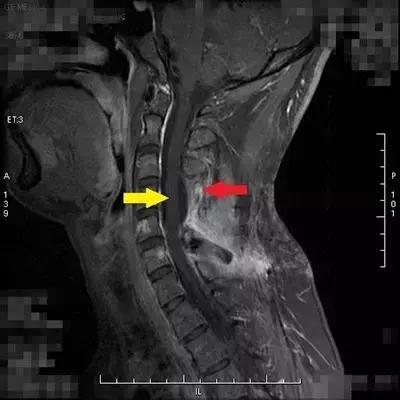

患者小康(化名)今年26岁,2013年查出椎管内肿瘤并进行切除,2015年12月复发到北京清华长庚医院就诊,经神经外科医师评估后再次行切除术,病理报告为间变型血管周细胞瘤。术后三个月复查,核磁共振扫描提示:C5-C6(“C”代表颈椎)水平椎管内硬膜外左侧及C5/6左侧椎间孔区仍可见实性强化影,考虑为肿瘤病变,建议行术后放射治疗。

北京清华长庚医院放疗科接诊后发现,小康的病变位置紧邻脊髓,常规放疗(X射线)容易造成脊髓受照超量,一旦超量,会导致神经系统严重并发症,放疗科医师建议小康行质子治疗。经与患者沟通后,联系台湾林口长庚质子中心医师进行远程会诊,并由台湾林口长庚纪念医院国际医疗中心个案管理师接管小康,全程协调安排其接受质子治疗。在台治疗结束后,小康回京定期到北京清华长庚医院复查、随访,目前状况良好,暂未发现肿瘤异常。